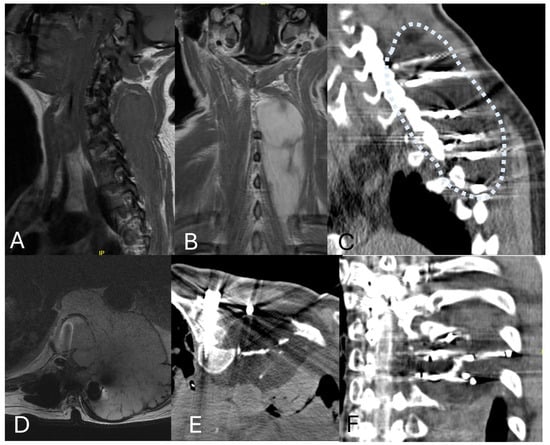

5. Laser Interstitial Thermal Therapy (LITT)

- Tatsui, C.E.; Lee, S.-H.; Amini, B.; Rao, G.; Suki, D.; Oro, M.; Brown, P.D.; Ghia, A.J.; Bhavsar, S.; Popat, K.; et al. Spinal Laser Interstitial Thermal Therapy: A Novel Alternative to Surgery for Metastatic Epidural Spinal Cord Compression. Neurosurgery 2016, 79, S73–S82. [Google Scholar] [CrossRef]

- Tatsui, C.E.; Stafford, R.J.; Li, J.; Sellin, J.N.; Amini, B.; Rao, G.; Suki, D.; Ghia, A.J.; Brown, P.; Lee, S.-H.; et al. Utilization of laser interstitial thermotherapy guided by real-time thermal MRI as an alternative to separation surgery in the management of spinal metastasis. J. Neurosurg. Spine 2015, 23, 400–411. [Google Scholar] [CrossRef]

- Tatsui, C.E.; Nascimento, C.N.G.; Suki, D.; Amini, B.; Li, J.; Ghia, A.J.; Thomas, J.G.; Stafford, R.J.; Rhines, L.D.; Cata, J.P.; et al. Image guidance based on MRI for spinal interstitial laser thermotherapy: Technical aspects and accuracy. J. Neurosurg. Spine 2017, 26, 605–612. [Google Scholar] [CrossRef]